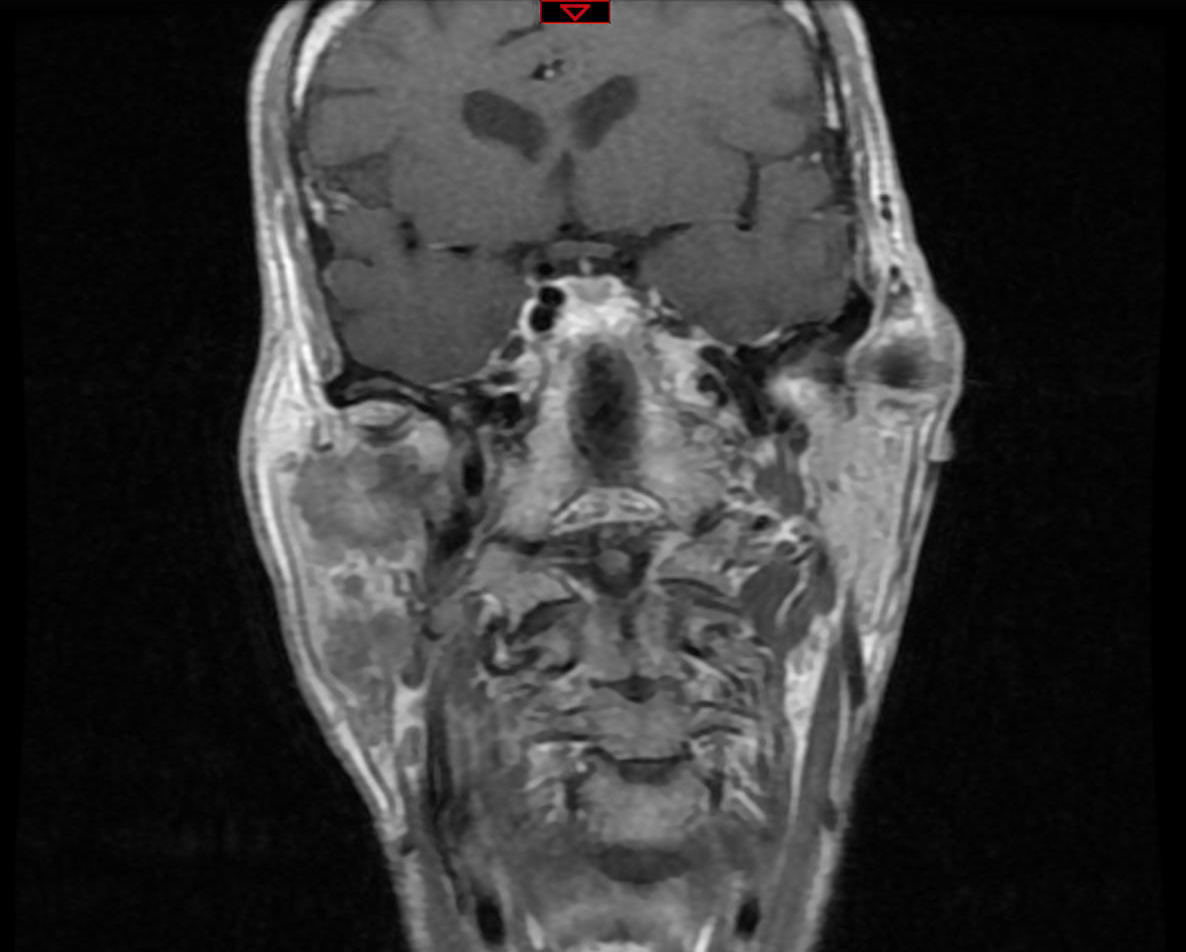

Elle a remarqué, depuis quelques mois, une « boule » en avant de l’oreille à droite, en regard du lobule. Elle n’a pas mal mais est un peu inquiète.

À rechercher devant toute pathologie de la région parotidienne. Un testing musculaire doit être réalisé. Sa présence oriente vers la malignité.

En cas de tumeur maligne, il peut exister des ganglions cervicaux.